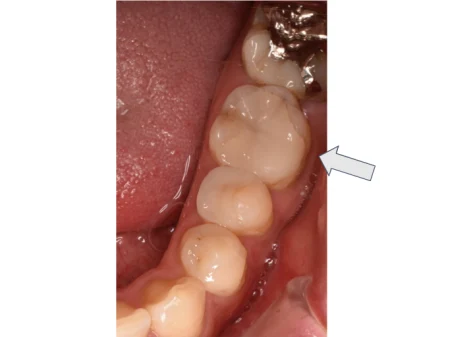

セラミック 2023.0330代女性「上の奥歯がしみて痛い」やや深い虫歯を取り除き、目立ちにくい白さで強度もあるセラミックの詰め物「E-maxインレー」で修復した症例